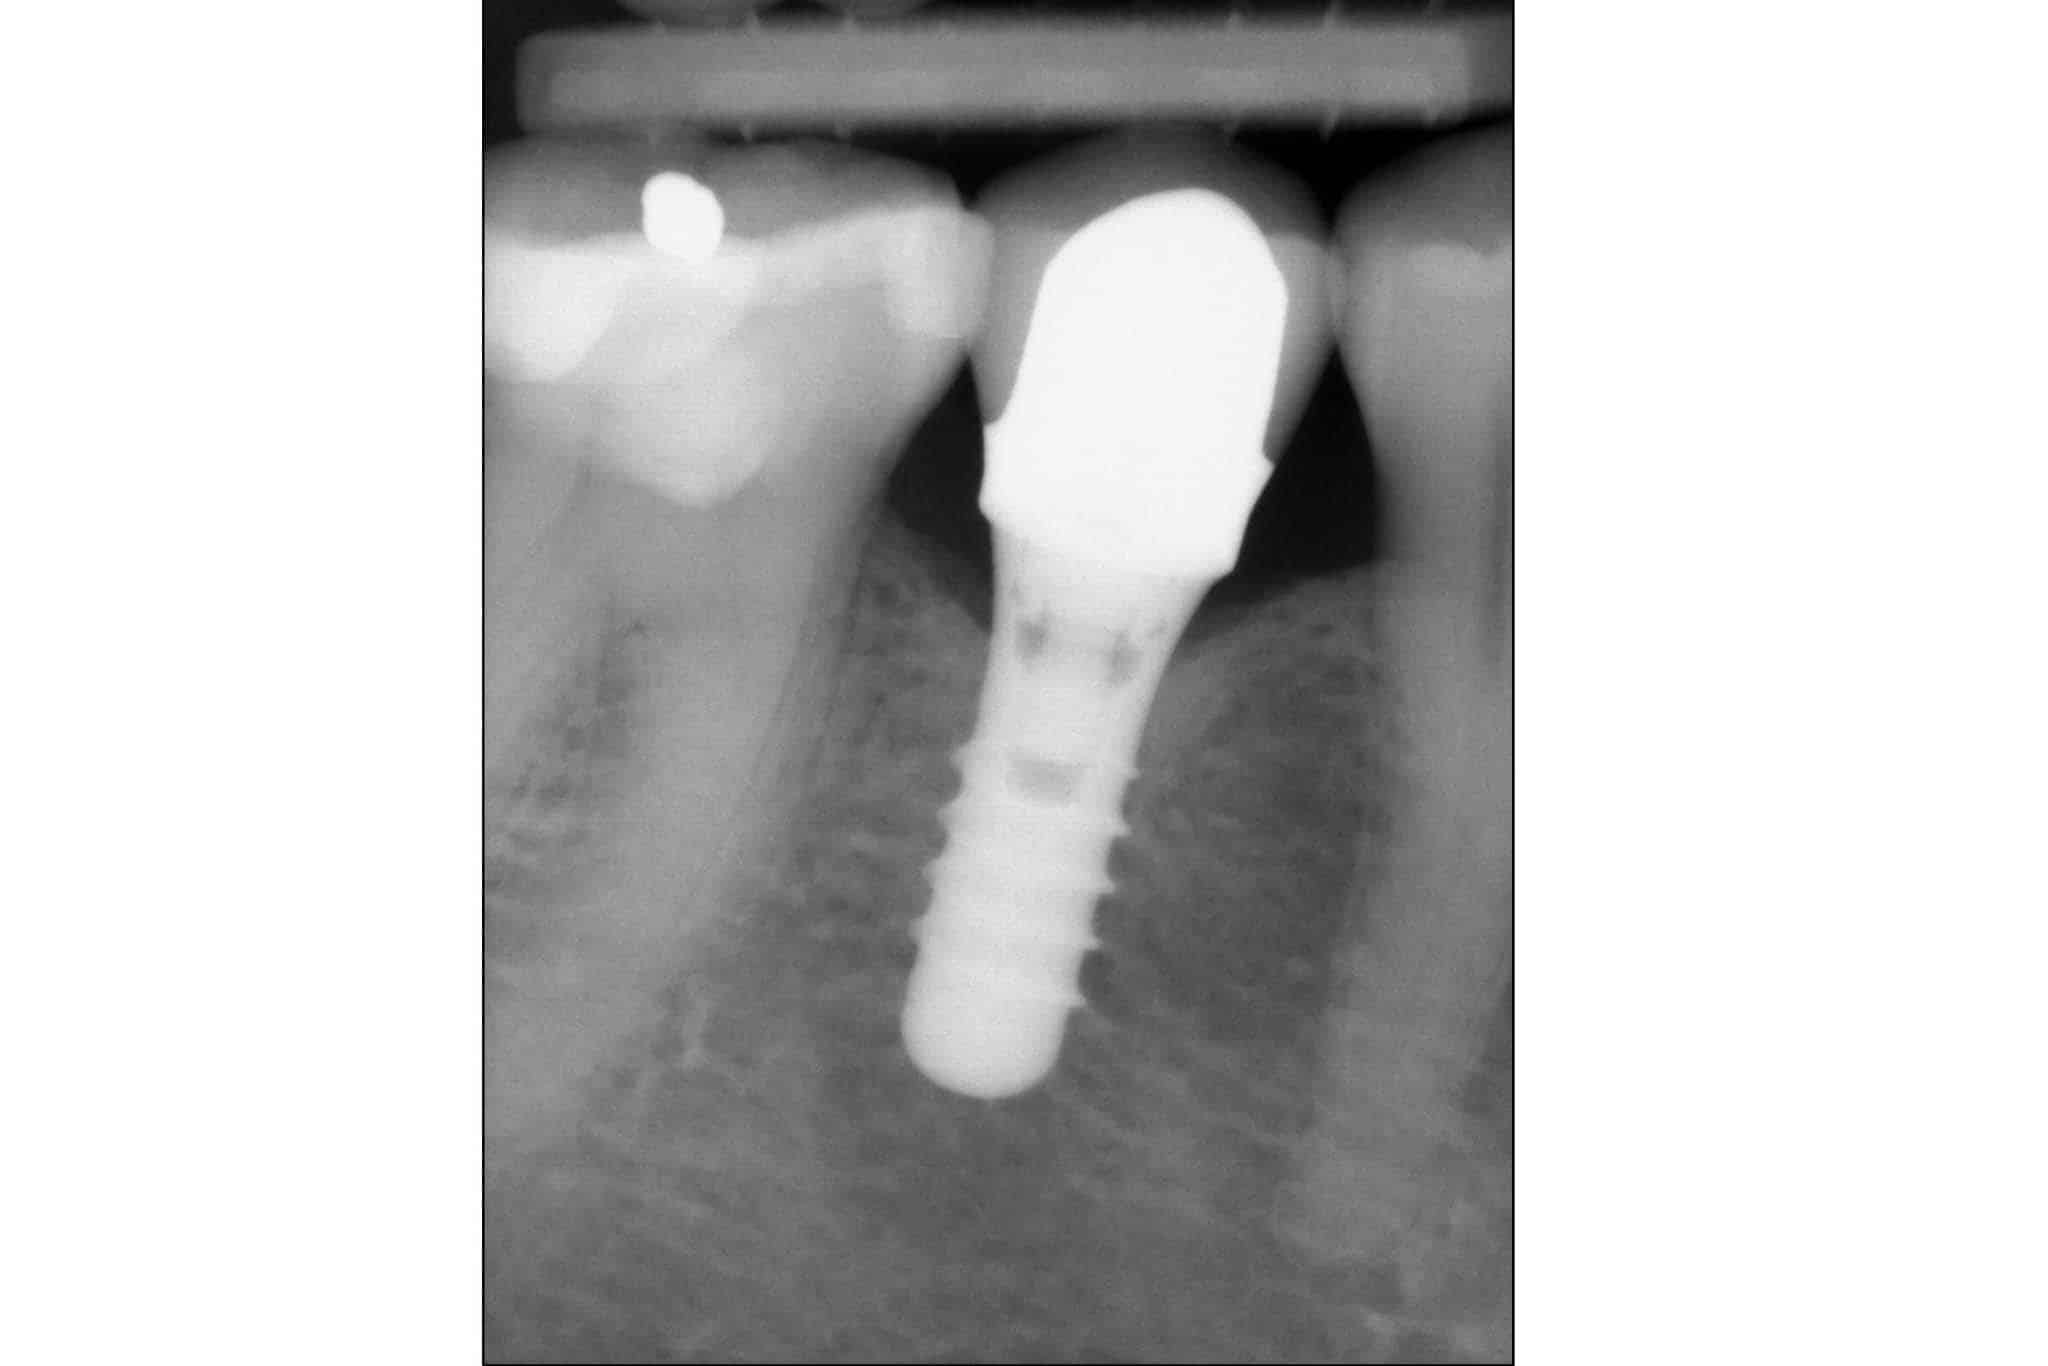

Et tannimplantat er en kunstig tannerstatning som likner mest i struktur på en ordinær tann. Et tannimplantat består hovedsakelig av to deler

- en kjevedel som forankres i kjevebenet (også kjent som fikstur)

- en tyggedel som festes over kjevedelen (navn avhengig av løsning).

Kjevedelen har form som en skrue, med gjenger, men uten en spiss tupp. Kjevedelen settes i kjevebenet, hvortil kjevebenet rundt vil vokse inn til denne og omsider forankre den. Når kjevedelen er klar til å belastes, festes tyggedelen til kjevedelen. Det finnes forskjellige tyggedeler som kan festes til kjevedelen, og disse skal vi introdusere lengre ned.

Kjevedel (innsetting og tilheling av fikstur)

Så snart det begynner å nærme seg tiden for å sette inn kjevedelen, vil det være behov for å hente inn informasjon for å planlegge inngrepet (plassering, produkt, forløp). Time til undersøkelser og røntgenbilder vi bli satt opp. Så snart det er avgjort, hvilket produkt skal brukes, i hvilken størrelse og hvordan inngrepet bør være, vil en ny time bli satt opp. Kjevedel settes inn etter plan, og nå vil området trenge å hvile i tre til fire måneder.